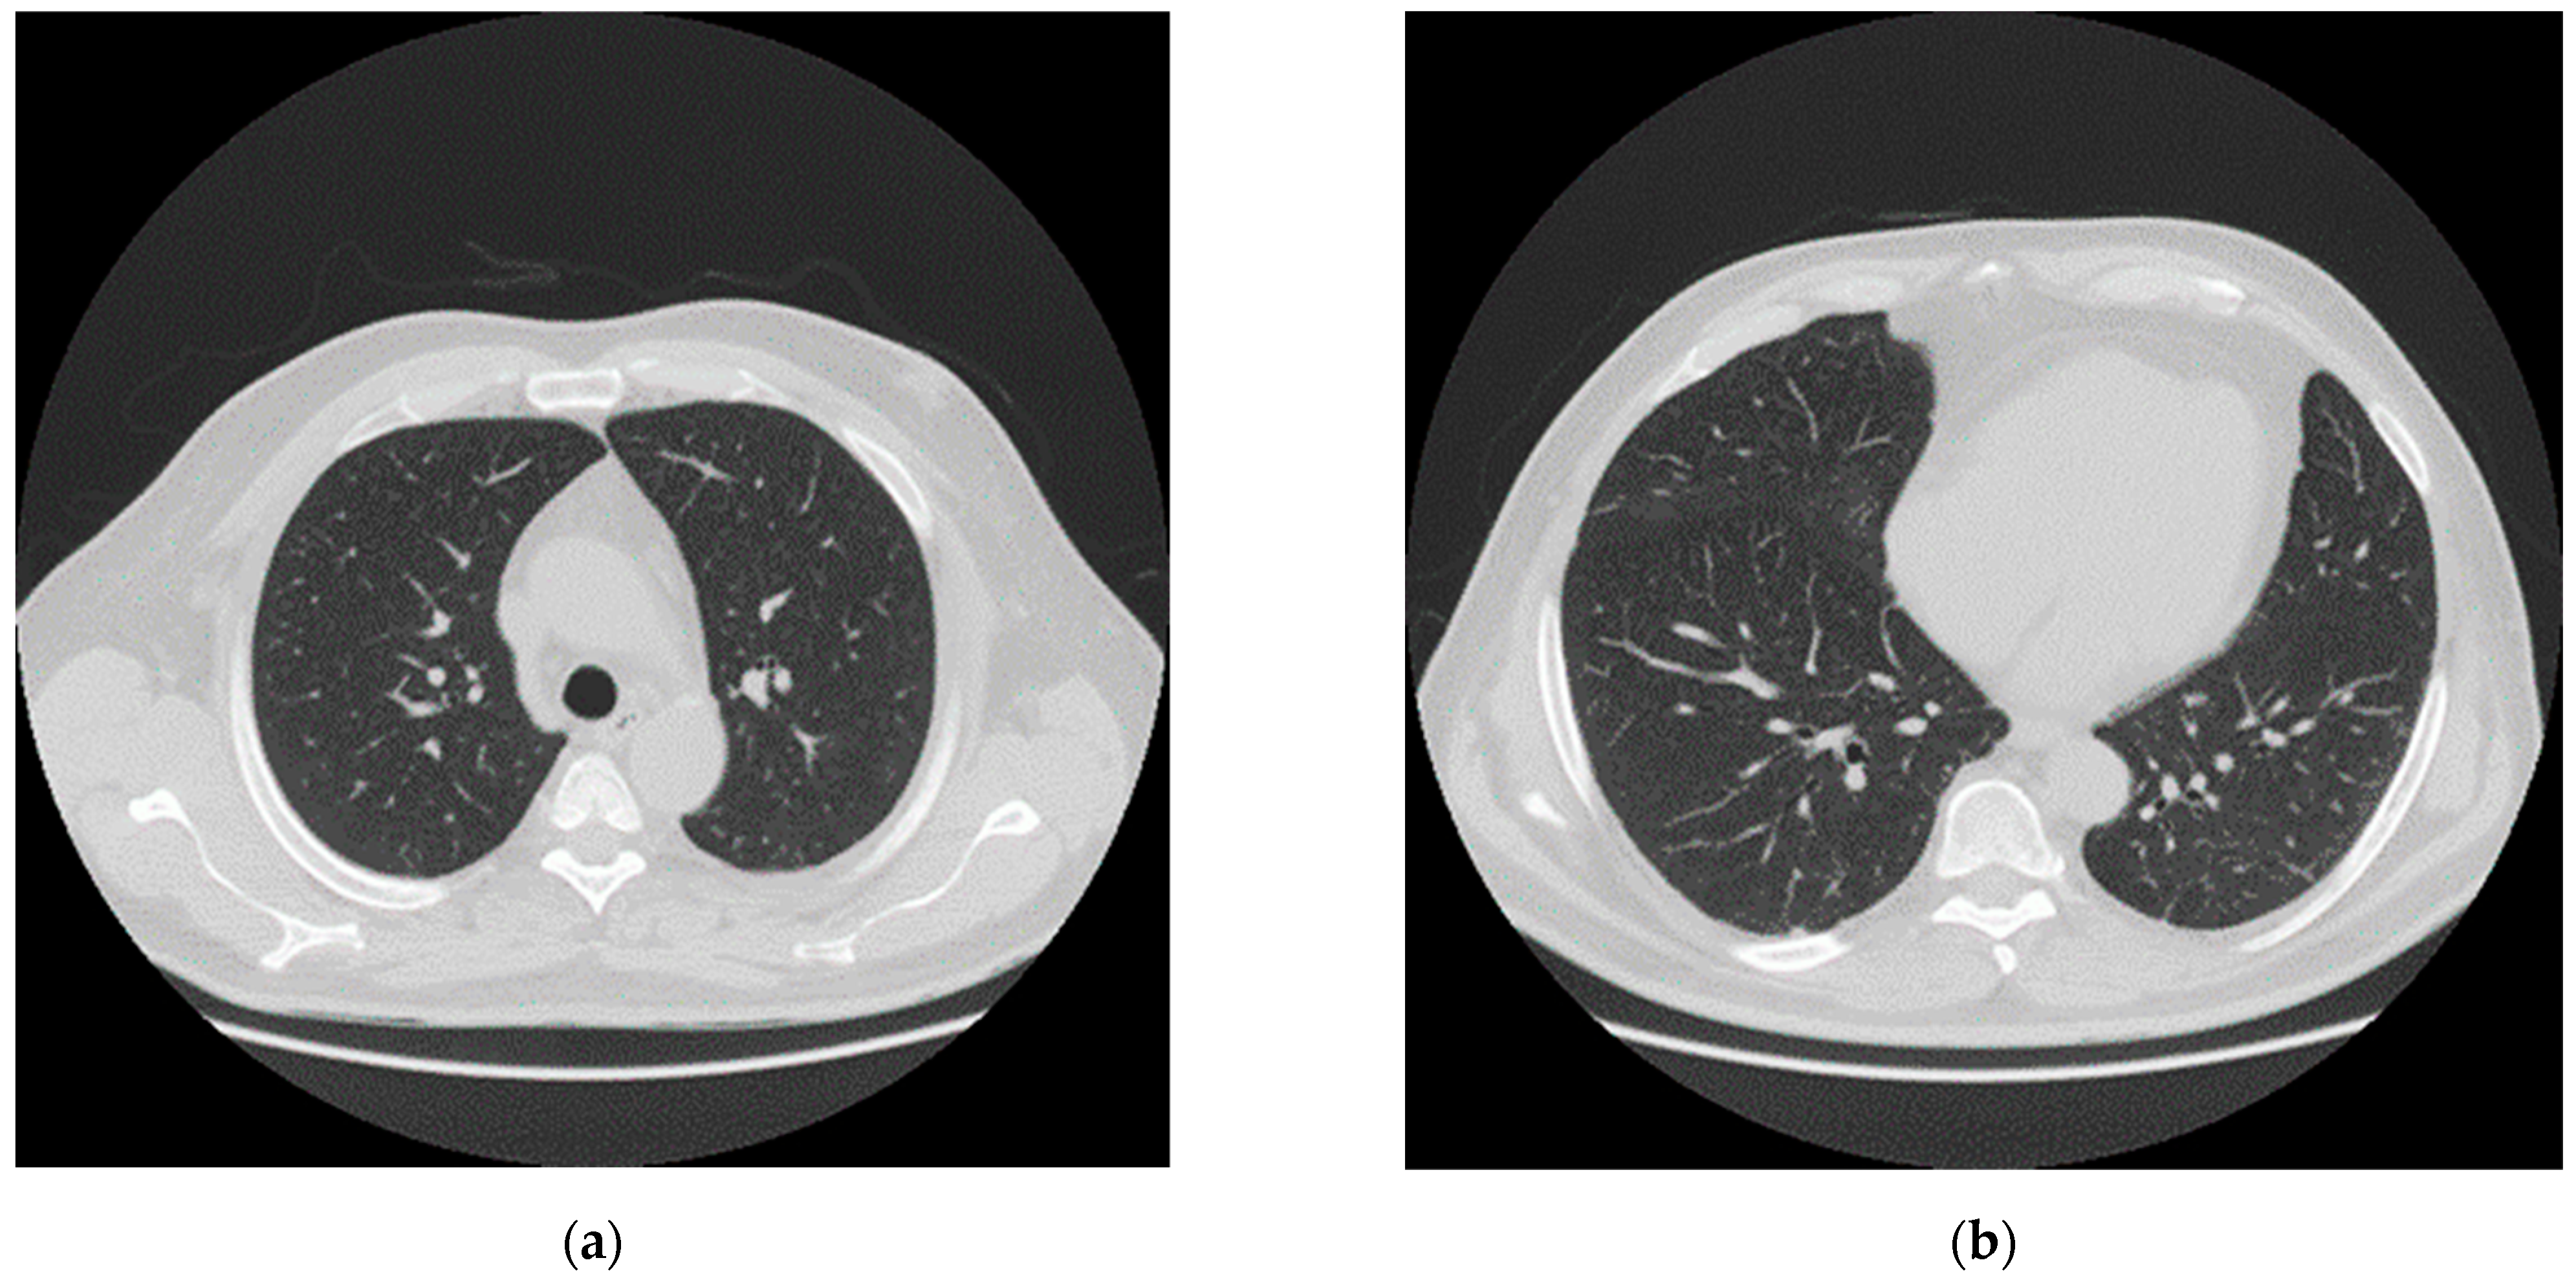

2.1. Hospital Phase